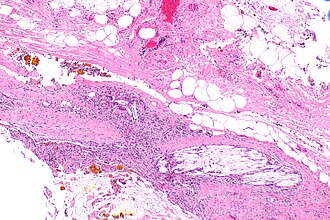

Xanthogranulomatous cholecystitis. H&E stain. | |

Features:[4]

- Granulomas.

- Lipid-laden macrophages.

- +/-Cholesterol clefts.

- Inflammatory cells.

- Fibrosis.

The sections show a thickened gallbladder wall with cholesterol clefts, multinucleated giant cells, fibrosis and lymphoid aggregates. No metaplasia, nuclear atypia or dysplasia is apparent.